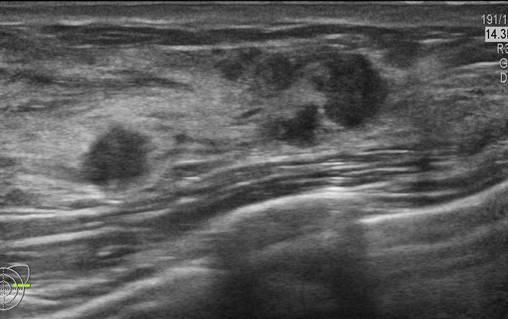

Ung thư vú

» Thông tin: Nữ giới – 25 tuổi.

» Lâm sàng: Khối tuyến vú.